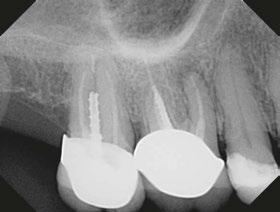

Case 1: Pre-op and diagnosis: A 68-year-old female presented with localized vestibular swelling buccal to tooth No. 30. No. 30 had been symptomatic for a few days, but the swelling started to alarm the patient and caused her to seek treatment. Upon evaluation, No. 30 was diagnosed as necrotic pulp with acute apical abscess. Two treatment options were discussed with the patient: 1) Tooth No. 30 non-surgical root canal therapy or 2) Tooth No. 30 extraction. The patient elected tooth No. 30 non-surgical root canal therapy (NSRCT). A pre-op Small FOV CBCT revealed a heavily calcified pulp chamber and calcified canals and a radix entomolaris. The CBCT revealed PARL’s at the apex of the mesial, distal, and radix entomolaris roots with the lesion extending coronally into the furcation. The patient was advised before treatment that this would be a very challenging case, and No. 30 NSRCT would be given a guarded prognosis, but she chose to proceed with No. 30 NSRCT. Treatment: No. 30 NSRCT, the patient was anesthetized with 68 mg Lidocaine with 0.034 mg EPI via IAN and 68 mg Septocaine with 0.017 mg EPI via buccal infiltration. Rubber dam isolation was utilized, and access was prepared through the PFM crown. 4 canals were located and then immediately after identification of the canal orifices, a platform was created with Soundseal, and the GentleWave Cleanflow handpiece was utilized to help break up the calcified tissue and negotiate each canal, alternating between a pathfile to slowly negotiate the coronal half of the canals and then running the GentleWave CleanFlow Procedure Instrument for 30-40 seconds to remove the accumulated debris. By alternating between files and the CleanFlow with GentleWave, all 4 canals were negotiated to length, and patency was achieved. The final working lengths were between 23 mm-24.5 mm for all 4 canals. All canals were instrumented to a Master Apical File of 20/.04 and obturated with high-flow BC Sealer. By utilizing the GentleWave and High-Flow BC Sealer, the apical delta of the distal root was cleaned, disinfected, and obturated in ways that would not have been possible with traditional endodontic therapy. Post-op: The patient was called 24 hours after treatment and reported she was pain-free, the swelling had reduced, and she was doing well.

9 endopracticeus.com Volume 17 Number 1 COVER STORY